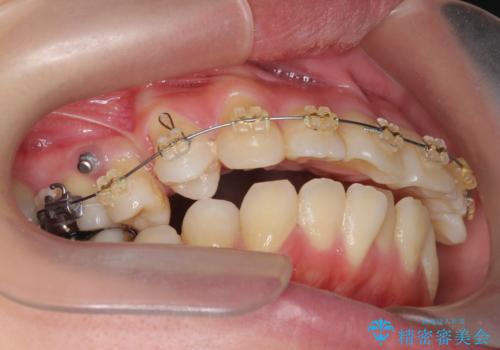

捻れた奥歯 突き出た前歯を治したい

- インビザライン +部分ワイヤー矯正

- 出っ歯に見える前歯、捻れてしまった小臼歯の改善を求めて来院されました。

マウスピースでは改善の難しい小臼歯のねじれをまず部分ワイヤー矯正で改善し、その後マウスピース矯正で前歯の突出感を改善します。